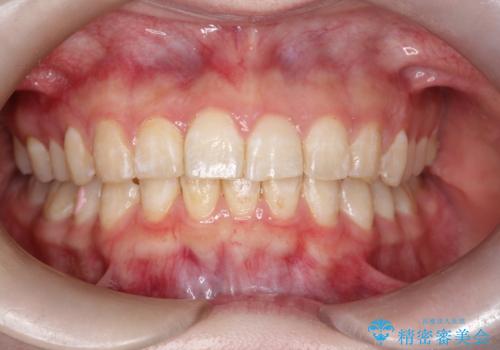

インビザラインで前歯のガタガタをきれいな歯並びへ

- 前歯のガタガタが気になるとのことで来院されました。

上顎の前歯の叢生があったのと、下あごの前歯が通常より1本欠損(先天欠損)していました。

上顎の歯と歯の間をわずかに削りスペースをつくり、並べる計画としました。インビザライン治療を選択されました。

しっかりとインビザラインを使用していただけたので、スムーズに治療を終了させることができました。